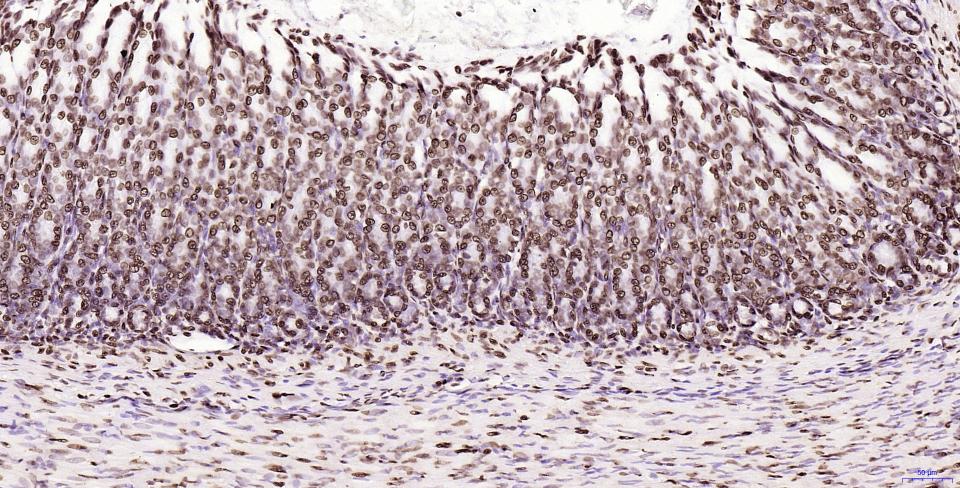

Paraformaldehyde-fixed, paraffin embedded Human Stomach; Antigen retrieval by boiling in sodium citrate buffer (pH6.0) for 15 min; Antibody incubation with Histone H2A.X Monoclonal Antibody, Unconjugated(bsm-61080R) at 1:200 overnight at 4°C, followed by conjugation to the SP Kit(Rabbit, SP-0023) and DAB (C-0010) staining.